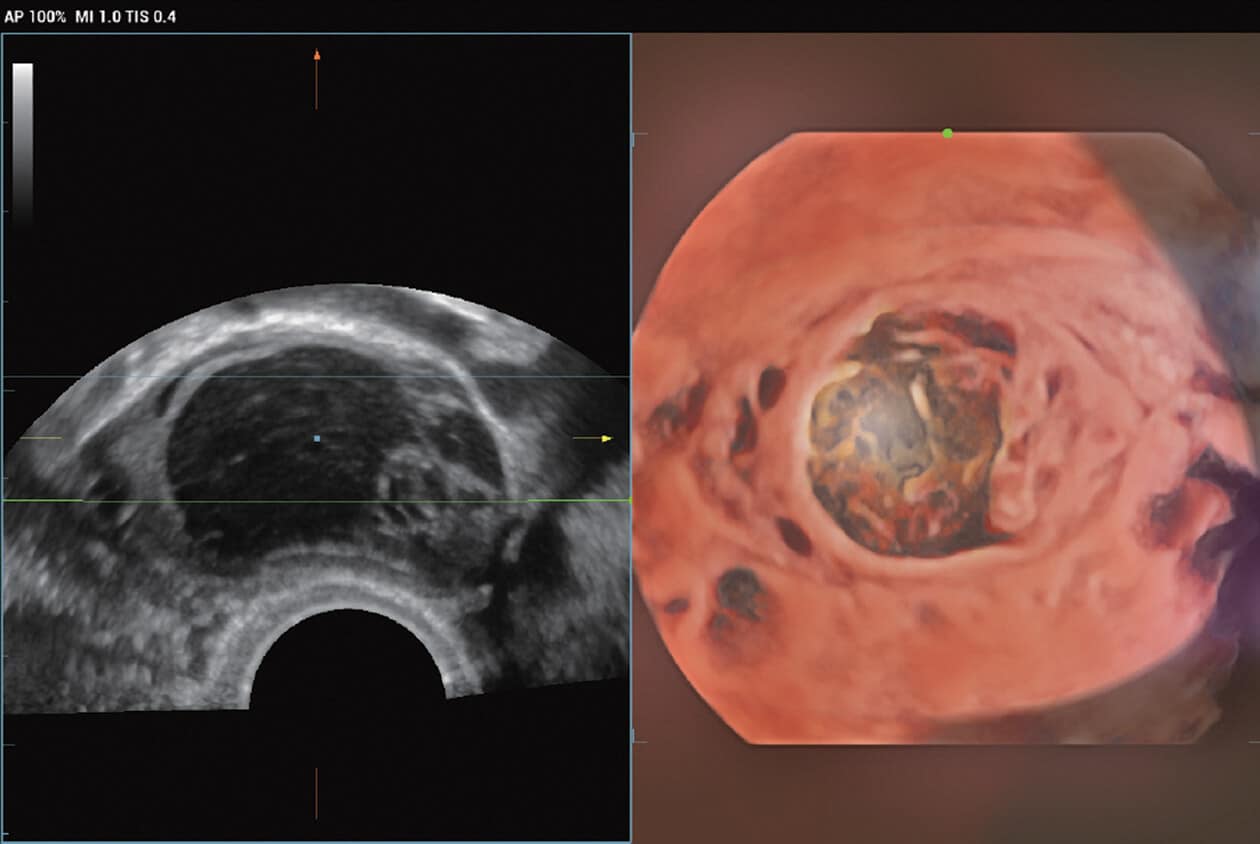

Powered by Mindray’s revolutionary ZONE Sonography (R) Technology+, the Imagyn I9 System boasts advanced ultrasound capabilities and leverages AI-inechanged technologies. The Imagyn I9 starts the process using auto clinical scenario identification, and uses automation at every point, from imaging optimization to planes scenario identification, and uses automation at every point, from imaging optimization to planes acquisition, quantification, and creating an automated workflow. The Imagyn I9 System provides a full-stack smart solution for efficient women’s health, covering wide-ranging applications from pre-pregnancy to obstetric to post-partum.